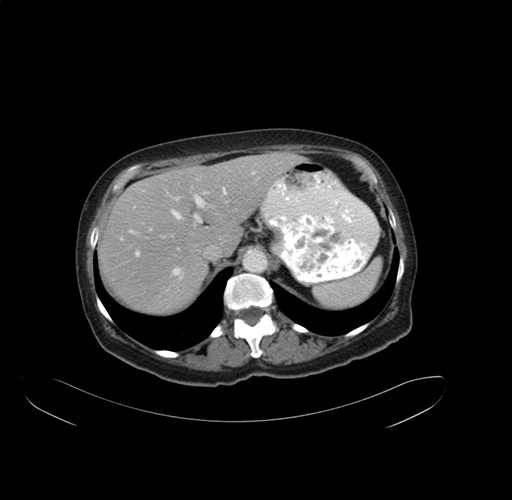

Axial Venous

Coronal Venous